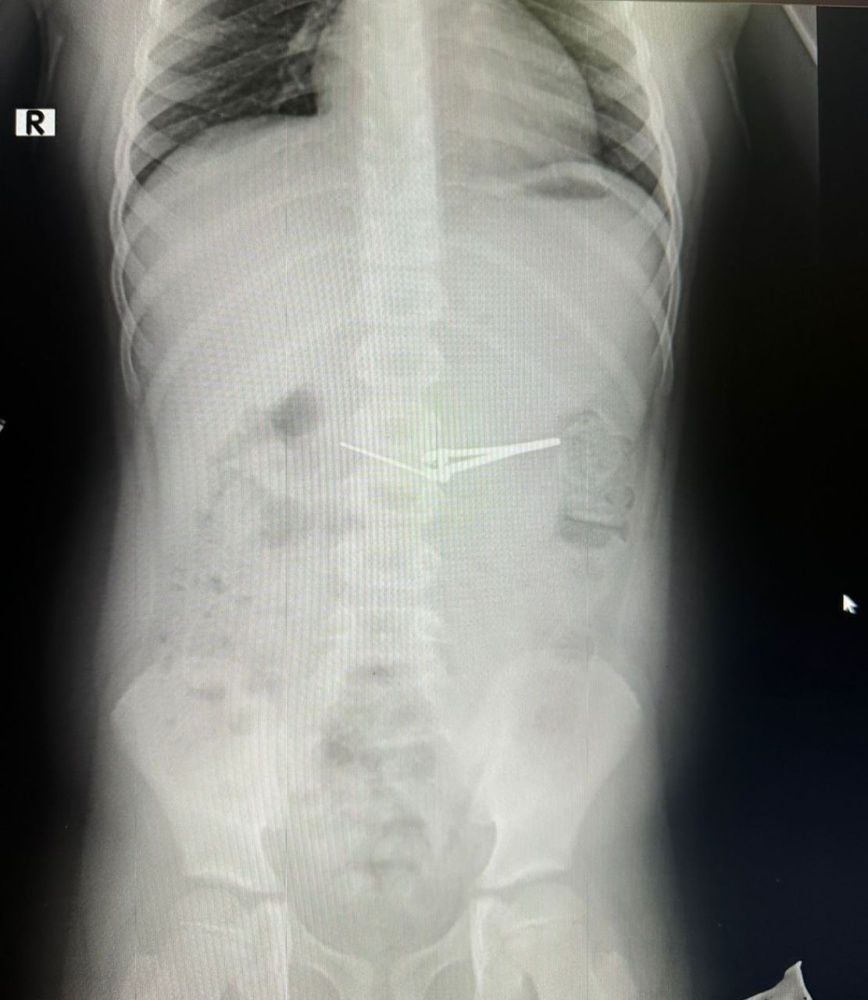

Врачи городской детской больницы №17 Уфы вытащили из желудка 6-летнего мальчика щипцы для стрижки ногтей

Для этого они использовали специальную корзину. По экстренным показаниям ребенку была проведена лечебная фиброгастроскопия под общим обезболиванием. Во время процедуры специалисты использовали специальное устройство — эндокорзину, что позволило аккуратно захватить и извлечь щипцы, не повредив слизистую оболочку желудка и пищевода.